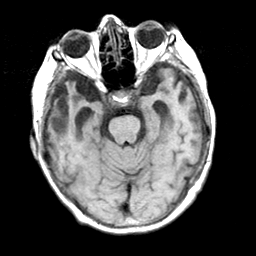

Pick's Disease, MR Study mr-t1 -- Slice #7

[Home][Help][Clinical] Slice 7